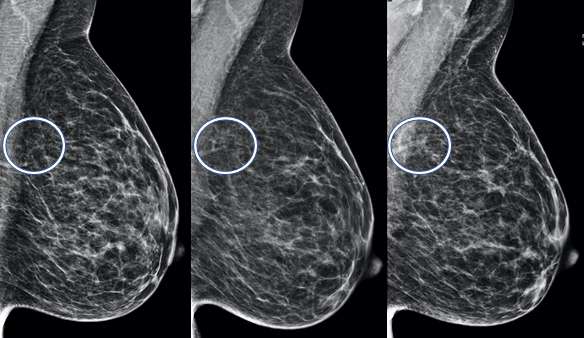

Asymmetry:

An asymmetry is a finding onlyseen on one projection3. Asymmetries that have been evaluated without suspicious features but persist are likely benign and can be managed with 6-month short-term imaging follow up.

MLO views of the breast demonstrate an asymmetry in the left subareolar breast, middle depth. This finding is called an asymmetry if there is no corresponding finding on the CC view.